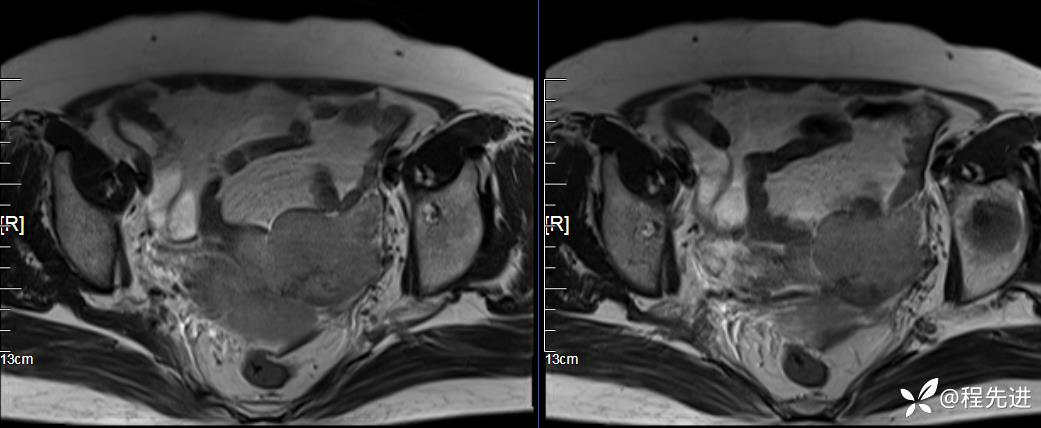

T2: